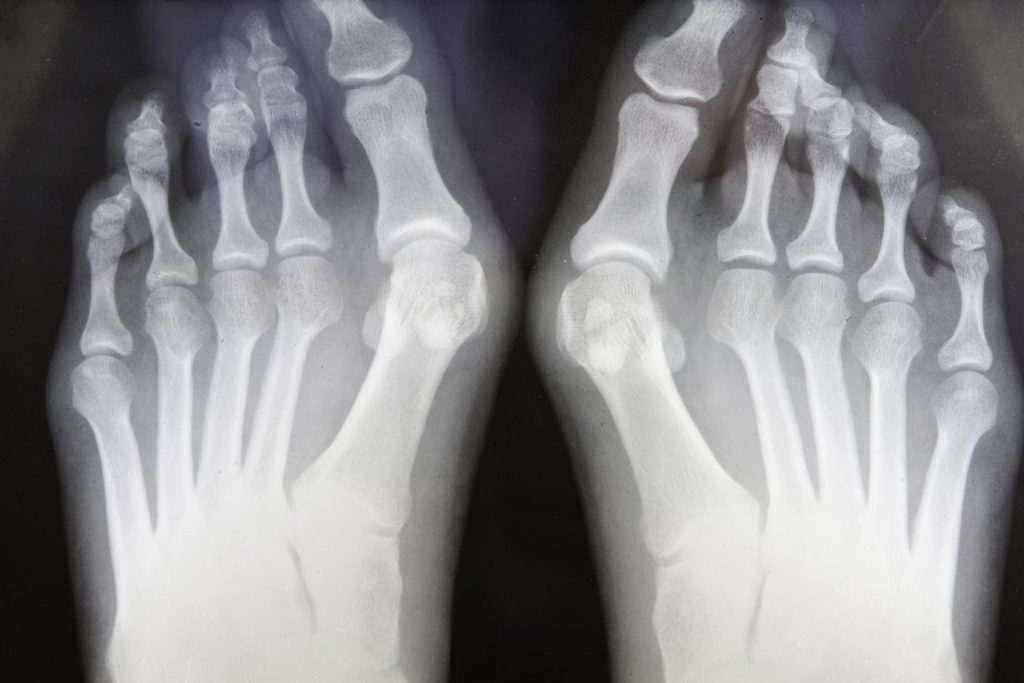

WebLa convalescenza di un intervento di metatarsalgia assume carattere variabile in base a molti fattori. Anche se le statistiche parlano di un range temporale che comprende un. WebSubito dopo l'intervento mi hanno detto di indossare le scarpe post operatorie (modello walk 1) ma i primi giorni proprio non riuscivo,avevo parecchio male e quando inserivo il. WebL’alluce valgo è una deformazione della giuntura metatarso/falange del primo dito del piede (l’alluce) che si manifesta con una rotazione di quest’ultimo, verso le altre dita, di almeno. WebL’ alluce valgo è una delle patologie più diffuse del piede. Si presenta come una deviazione laterale dell’alluce che, inclinandosi progressivamente verso le altre dita, determina a. WebDopo un intervento chirurgico di correzione di alluce valgo, dita a martello, metatarsalgie o altre patologie del piede meno diffuse, il principale problema rimane.

WebL’ alluce valgo è una delle patologie più diffuse del piede. Si presenta come una deviazione laterale dell’alluce che, inclinandosi progressivamente verso le altre dita, determina a. WebDopo un intervento chirurgico di correzione di alluce valgo, dita a martello, metatarsalgie o altre patologie del piede meno diffuse, il principale problema rimane. WebLa seguo dal 2003, da quando l’ho vista eseguire in diretta tv un intervento nel trattamento chirurgico dell’alluce valgo con la nuova tecnica percutanea mininvasiva..